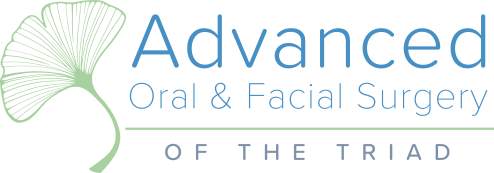

It amazes us how well people can heal sometimes. This case, done by Dr. Wes Parker, involved a 45 year old male who was referred for a carious, necrotic (dead) tooth #14 (upper left first molar). The patient also reported left sided sinus pressure and drainage. At his consultation, we obtained a Cone Beam CT (CBCT) scan. On his CBCT, you could see where the infection and inflammation from tooth #14 had eroded through the floor of the left maxillary sinus. We discussed this with him and scheduled surgery shortly after the consultation. Dr. Parker removed tooth #14, cleaned out the pus and inflamed maxillary sinus lining through the socket. The inflamed, thickened sinus lining went almost up to the orbit (eye socket). Dr. Parker then closed off the sinus communication. Following this, Dr. Parker placed a bone graft over the sinus closure, and then sutured over that to close the wound. The patient healed very well. He was compliant with the sinus precautions and medications that were prescribed. Next, Dr. Parker proceeded with implant placement in the #14 site with a simultaneous indirect sinus lift or “sinus bump.” The implant placement surgery went well, and after about 5 months of healing time, the patient received a crown on the implant from his dentist. Image #1 is a preoperative PA radiograph of the carious, necrotic, nonrestorable tooth #14 (upper left first molar). Image #2 is a coronal slice from the patient’s preoperative CBCT showing the necrotic tooth #14 with a periapical radiolucency and maxillary sinus inflammation stemming from the necrotic tooth. Image #3 is a sagittal slice from the patient’s preoperative CBCT showing the necrotic tooth #14 with a periapical radiolucency and maxillary sinus inflammation stemming from the necrotic tooth. Image #4 is a sagittal CBCT slice from the patient’s post extraction CBCT showing resolution of the sinus inflammation and measurements for the future dental implant. Image #5 is an immediate postoperative PA of the implant in the #14 site following implant placement with a simultaneous indirect sinus lift. Image #6 is a 5 month postoperative PA showing the healed, integrated implant prior to crown placement with a healed sinus lift bone graft above it and no sinus inflammation.